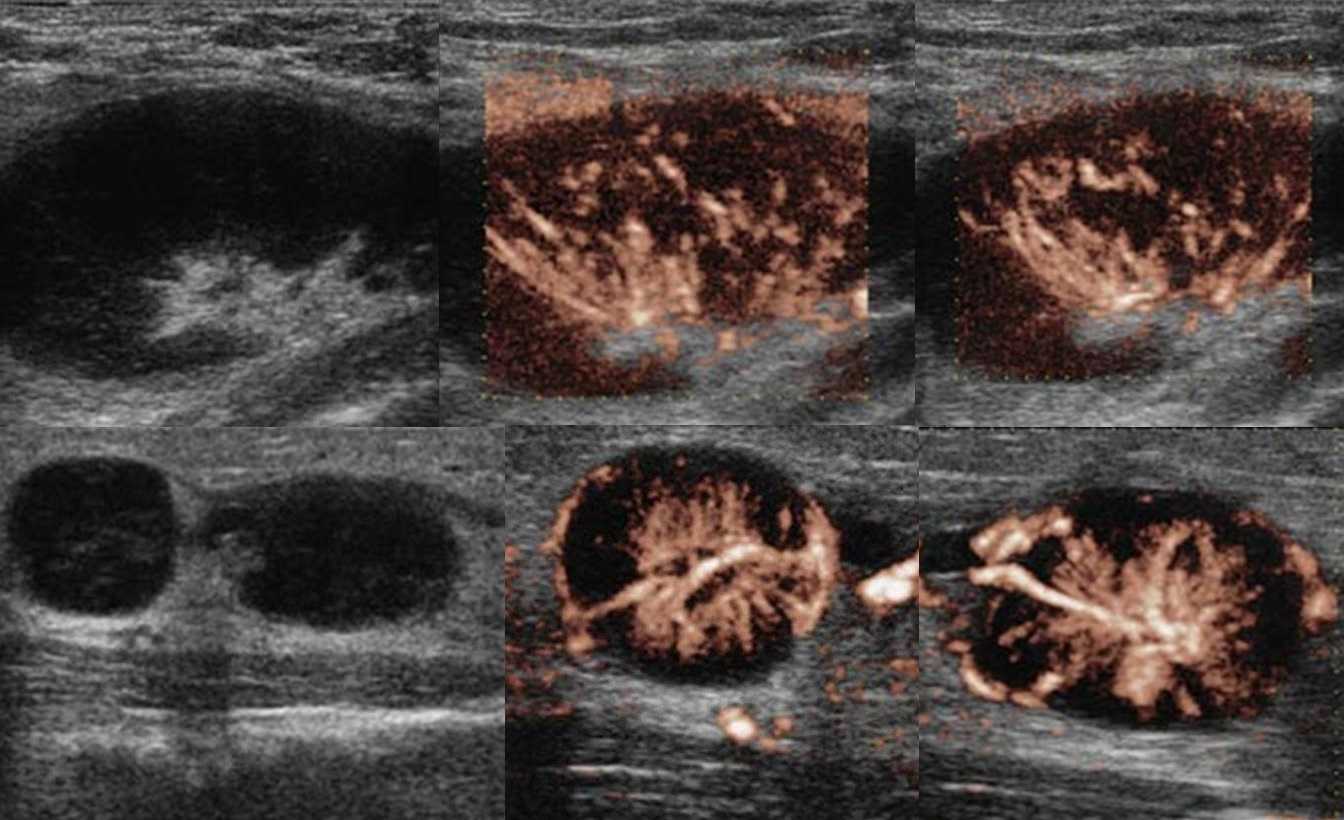

Рисунок. На УЗИ лимфоузлы увеличены, овальной формы, четкий и ровный контур, эхогенность пониженная, корковая зона несколько расширена, центральный рубчик видно отчетливо; кровоток в воротах усилен, сосуды расположены правильно — расходятся радиально, подкапсульный кровоток не определяется. Заключение: Лимфаденопатия с признаками высокой степени активности.

Рисунок. Ребенок с высокой температурой, ангиной и двусторонней «опухолью» на шее, в общем анализе крови атипичные мононуклеары 25%. На УЗИ передне- и заднешейные лимфоузлы увеличены (максимальный размер 30х15 мм), округлой формы, неоднородные

Обратите внимание, центральный рубчик отлично видно, а кровоток на уровне ворот усилен. Заключение: Лимфаденопатия с признаками высокой степени активности

Большие группы увеличенных лимфоузлов на шее характерны для инфекционного мононуклеоза. Учитывая течение болезни и наличие атипичных мононуклеаров, вероятно, у ребенка инфекционный мононуклеоз.

Рисунок. Женщина жалуется на «опухоль» в подмышке и на локте. Неделю назад повздорила с соседской кошкой. На УЗИ подмышечный (сверху) и локтевые (снизу) лимфоузлы увеличены, округлой формы, выраженная гиперплазия корковой и околокорковой зоны, гиперэхогенный центральный рубчик сохранен; кровоток заметно усилен, сосуды расположены правильно — радиально. Заключение: Лимфаденопатия с признаками высокой степени активности. При болезни кошачьей царапины на месте укуса или царапины образуются небольшие гнойнички и одновременно воспаляются близкие лимфоузлы. Один или группа лимфоузлов увеличиваются в размерах до 5-10 см, становятся болезненными, уплотняются. Через 2-4 недели происходит самоизлечение. Иногда образуются абсцессы и свищи.